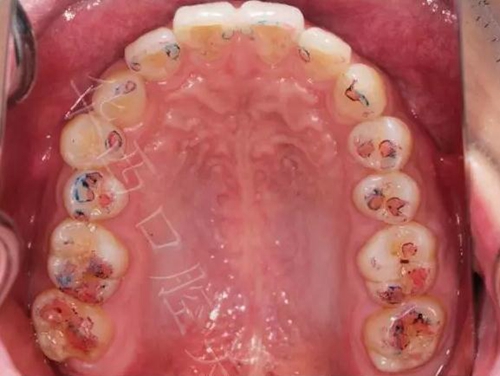

①咬住200微米藍色咬合紙,前后左右磨,

▲ 圖5:200μm咬合紙

▲圖6:200µm 功能運動